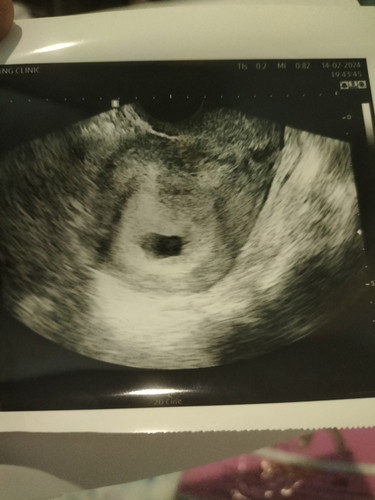

เบบี๋ของแม่หลบอยุ่ไหน

7 วีค 5วัน ยังไม่เจอตัวน้องหมอสันนิษฐานว่าจะเป็นท้องลม แม่ๆเจอน้องช้าสุดกี่วีคค่ะ

ของเค้า7วีค3วันค่ะ เจอตัวน้องและได้ฟังเสียงหัวใจเต้นแล้ว คุณแม่ทำใจสบายๆนะคะ รอซาวด์ครั้งหน้า น้องอาจจะตัวเล็ก เลยยังไม่เจอค่ะ

บางคนซาวเจอตอน10weekก็มีนะคะเดม่ไปอ่านเจอ